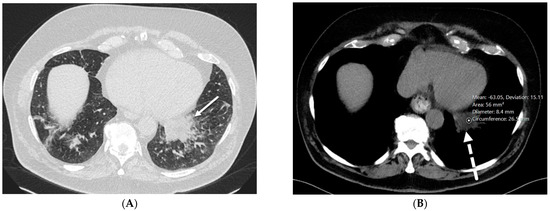

4.7. Pulmonary Vein Stenosis (PVS)

7.2. Pulmonary Capillary Hemangiomatosis (PCH) and Pulmonary Veno-Occlusive Disease (PVOD)